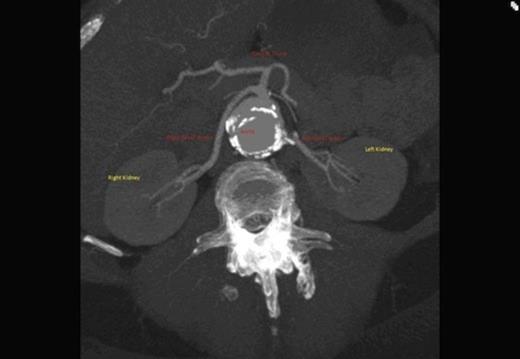

A CT scan revealed an aneurysmal distal thoracic aorta measuring 40mm and 49mm at the level of the diaphragm and of normal calibre at the left renal artery. The right renal artery very interestingly had its origin from the coeliac axis with no significant renal artery disease and the left renal artery showed calcific disease with post-stenotic dilatation at its ostium from the aorta. There were also no accessory renal vessels noted.